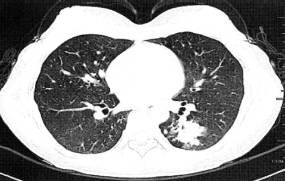

(1)周围型肺癌基本X线表现为肺内孤立的球形灶,不同组织类型的肺癌在大小、 医学百科网 | YxBaike.Com

密度、边缘形态及瘤体周围特点有一定差异。CT的优势在于可显示瘤体内密度、坏死、血供特点及临近结构浸润情况。除边缘凹凸不平,呈分叶征外,常可见边缘毛刺、瘤周血管集束征、胸膜凹陷征、内部空洞形成,多壁厚薄不均,内缘凹凸不平或见壁结节。无或少有气液平为其特征(图2)。增强检查病灶可见明显强化,CT值增加25Hu以上。高度提示 肺癌。 医学百科网 | YxBaike.Com